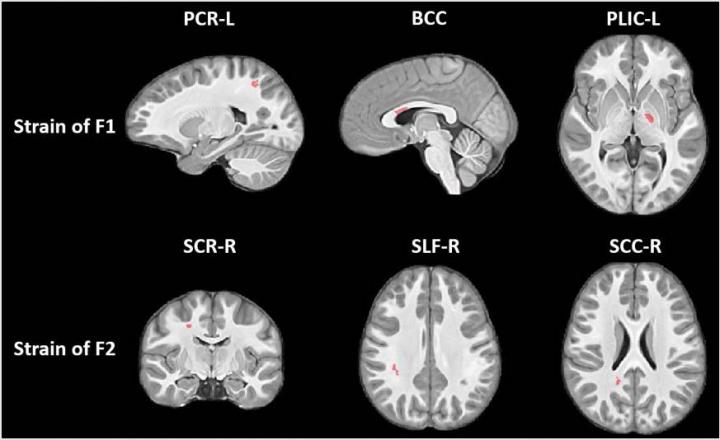

Dr. Kim and colleagues studied the results of these collisions on youth football players using a novel MRI method that looks at the strain evident on white matter tracts--the bundles of nerve fibers that carry information between different areas of the brain.

"The focus here was on deformations of these fiber bundles," Dr. Kim said. "Changes from collisions might cause elongation or contraction of these bundles."

The MRI results showed that the football players developed changes in the corpus callosum, a critically important band of nerve fibers that connects the two halves of the brain. The primary role of the corpus callosum is to integrate cognitive, motor and sensory functions between the two sides of the brain.

There were signs of greater axial strain (contraction) in some parts of the corpus callosum, and indications of radial strain (expansion) in other parts.

"The body of the corpus callosum is a unique structure that's somewhat like a bridge connecting the left and right hemispheres of brain," Dr. Kim said. "When it's subjected to external forces, some areas will contract and others will expand, just like when a bridge is twisting in the wind."